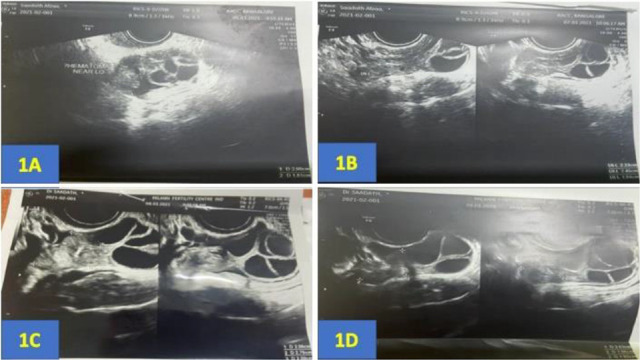

Case presentation: A rare case of periovarian hematoma was reported in a patient with a history of endometriosis undergoing ovarian stimulation for in vitro fertilization. On the seventh day of stimulation, the patient complained of severe pain in the abdomen. Her vitals and blood investigations were within normal limits. On abdominal examination, mild tenderness was noted in the left iliac fossa. On vaginal examination, fullness and tenderness were noted in the left fornix. On ultrasound, probe tenderness was present and a left ovarian hematoma measuring 2.0×1.81×1.55 cm was observed. She was managed conservatively. The hematoma exhibited a gradual reduction following the pick-up procedure and eventually resolved completely within a month.

Conclusion: Underlying endometriosis could be one of the possible causes of this periovarian hematoma. A conservative approach with close monitoring forms the first-line management in hemodynamically stable patients.